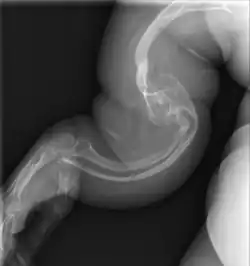

Type II

Collagen is fatally defective at its C-terminus.[5]: 1512 Most cases result in death shortly after birth, or within the first year of life, due to respiratory failure. Another common cause of death is intracranial bleeds from skull fractures present at, or sustained during or shortly after, birth.[5]: 1511 In many cases, the newborn already has multiple broken bones at the time of birth. Type II infants also exhibit severe respiratory problems and have severely deformed bones. Sixty percent of infants die less than 24 hours after being born, and survival after the first year is extremely unlikely and normally requires mechanical ventilation.[57] In the rare cases of infants who survive their first year of life, severe developmental and motor delays are seen; neither of two infants studied in 2019, both aged around two years, had achieved head control, and both required a ventilator to breathe.[58]

Type II is also known as the "lethal perinatal" form of OI,[59] and is not compatible with survival into adulthood.[57] Due to similarly severely deformed bones, sometimes infants with severe type III are wrongly initially classified as type II; once long-term survival is shown, they are considered as having type III instead.[5]: 1511 [60]

An OI diagnosis can be confirmed through DNA or collagen protein analysis, but in many cases, the occurrence of bone fractures with little trauma and the presence of other clinical features such as blue sclerae are sufficient for a diagnosis. A skin biopsy can be performed to determine the structure and quantity of type I collagen. While DNA testing can confirm the diagnosis, it cannot absolutely exclude it because not all mutations causing OI are yet known and/or tested for.[83]: 491–492 OI type II is often diagnosed by ultrasound during pregnancy, where already multiple fractures and other characteristic features may be visible. Relative to control, OI cortical bone shows increased porosity, canal diameter, and connectivity in micro-computed tomography.[98] OI can also be detected before birth by using an in vitro genetic testing technique such as amniocentresis.[99]